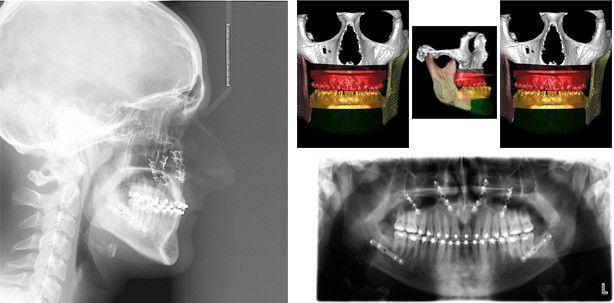

Im Unterkiefer erfolgt die Schnittführung im Zahnfleisch hinter dem letzten Backenzahn beidseits. Nun wird der Unterkiefer mit spezieller Technik durchtrennt. Dies erlaubt eine Verschiebung der zahntragenden Basis vom gelenktragenden Knochenabschnitt des Unterkiefers. Bei der Präparation wird der im Unterkieferknochen verlaufende Gefühlsnerv der Unterlippe sorgfältig geschont. Die neue Position wird mit einem zweiten Bissschlüssel, der die endgültige Bisssituation einstellt, zugeordnet und mit Osteosyntheseplatten und -schrauben gesichert. Die Platten und Schrauben fixieren den Knochen in der Art und Weise, dass der Patient postoperativ weiche Kost essen darf. Nach einer Woche werden die Fäden entfernt, die kieferorthopädische Feineinstellung des Bisses kann dann durchgeführt werden. Die Abbildung 2 stellt die Röntgenkontrolle in 2 Ebenen nach der OP dar.

Operationsplanung anhand der Daten der dreidimensionalen Röntgenaufnahmen: Jeweils vor (links) und nach der OP (rechts). Obere Reihe Frontalansicht, untere Reihe seitliche Ansicht. Der Oberkiefer wurde virtuell nach vorne verlagert, der Unterkiefer wurde zurückverlagert. (Quelle: Klinik für MKG-Chirurgie Klinikum Stuttgart, Katharinenhospital)